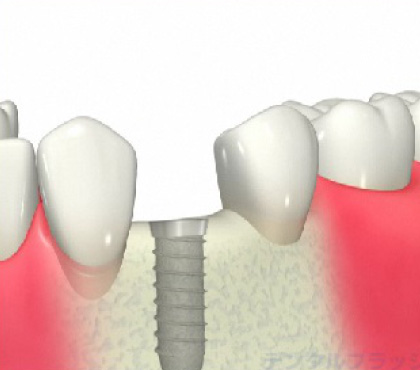

インプラント治療とは?

歯が抜けてしまったところの骨にフィクスチャー(ネジ)を 埋め込んで、そのネジを土台にして人工の歯を装着する治療法です。

1本歯を失ったら

歯を失った場合、従来の治療法では、隣の歯を削ってブリッジにするか残っている歯にバネをかけて取り外し式の入れ歯にする方法がとられていました。

■隣同士の歯を削らずに処置ができます。